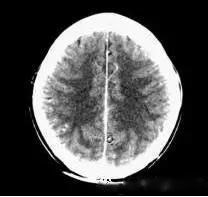

機(jī)器故障偽影是由于設(shè)備運行不穩(wěn)定或某一元器件損壞所造成。如探測器之間的響應(yīng)不一致,可造成環(huán)狀偽影;投影數(shù)據(jù)測量轉(zhuǎn)換誤差,可導(dǎo)致直線狀偽影;采樣頻率較低也可產(chǎn)生直線狀偽影;射線化效應(yīng),則可產(chǎn)生寬條狀偽影。依照CT的構(gòu)成,機(jī)器故障偽影大致來自以下幾個方面:

(機(jī)器故障偽影:常為環(huán)形或同心圓狀高密度偽影)

2、機(jī)器故障偽影的形狀機(jī)器故障所至偽影的形狀各種各樣,有非同心圓形和同心圓形(單同心圓和多同心圓、直線形、柵格形條紋狀)、星狀,還有不規(guī)則形,一般來說.根據(jù)偽影形狀可大致區(qū)分為機(jī)器哪一個系統(tǒng)故障所致。

如:單同心圓可能為通道板故障、連續(xù)屏蔽多個通道,多同心圓可能為環(huán)境溫濕度變化較大,AD控制板故障、線性電源問題、高壓線性電源問,滿屏斜條或直線可能為高壓系統(tǒng)故障·不規(guī)則形則可能為球管老化所致。